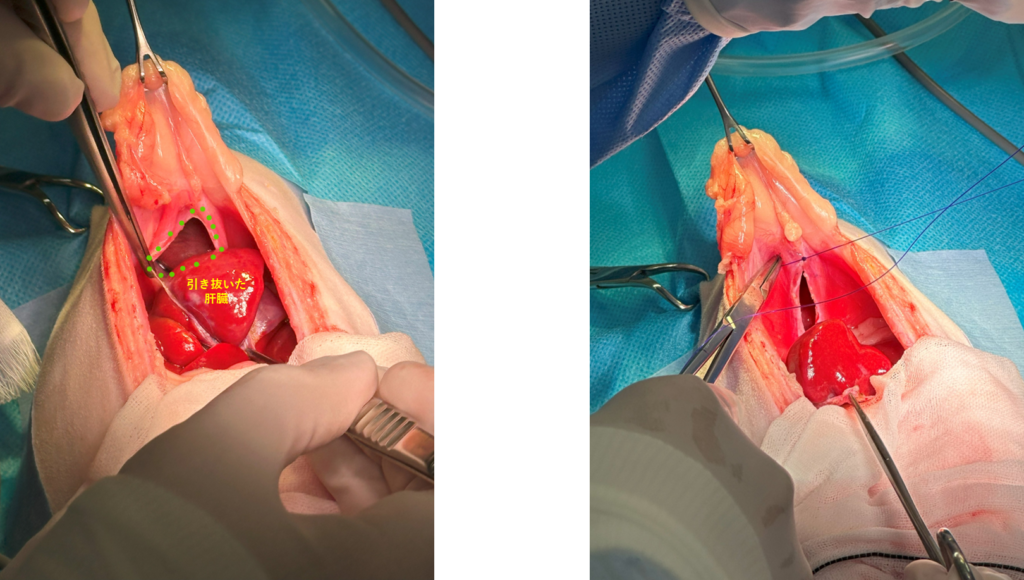

ヘルニア孔をみつけて胸の中に入り込んでいる肝臓を引き出します。

肝臓を戻したらヘルニア孔を縫合して閉じていきます。